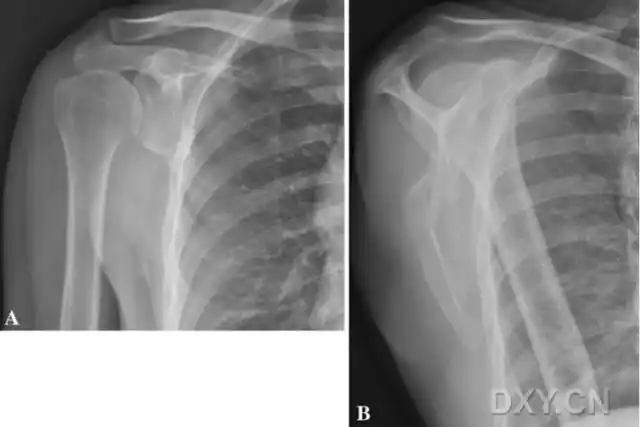

不同肩关节x线投照位

位片投照要点*广东省中医院大学城运动创伤关节镜专科 写美篇肩部创伤

不同肩关节x线投照位ppt课件